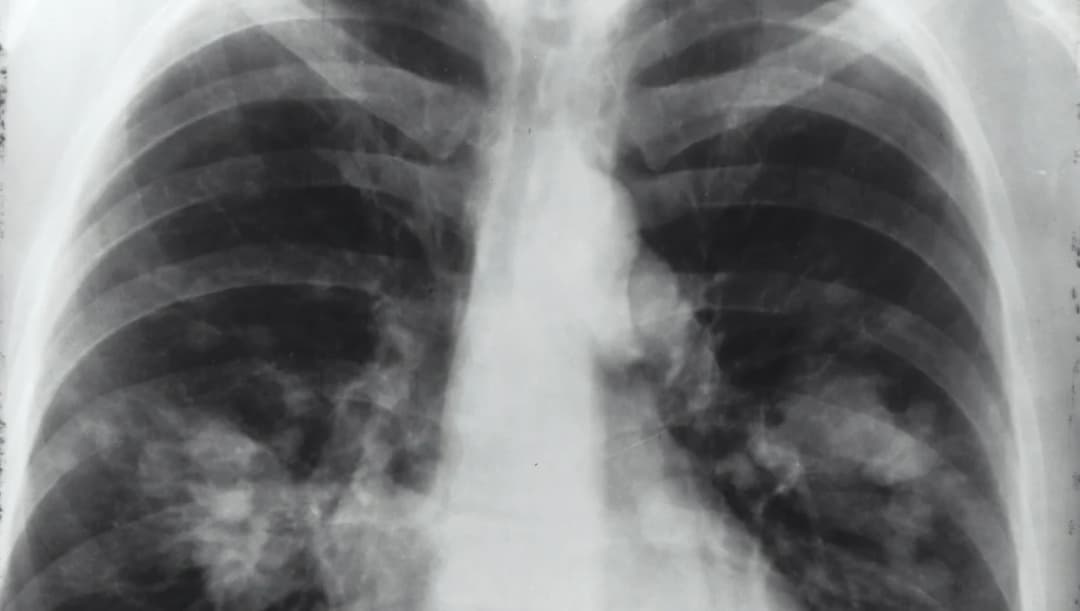

สธ. เผยข้อมูลมะเร็งปอดภาคเหนือ นายกฯ สั่งยกระดับแก้วิกฤติ pm 2.5 จับคนเผา-ตัดสิทธิ์ช่วยเหลือ9 เม.ย. 2567

เปิดสถิติ ‘มะเร็งปอด’ ในเชียงใหม่-ภาคเหนือ สูงกว่าภาคอื่น ข้อมูลวิจัยพบชนิดของมะเร็งปอดเกี่ยวข้องกับ PM2.511 พ.ย. 2565